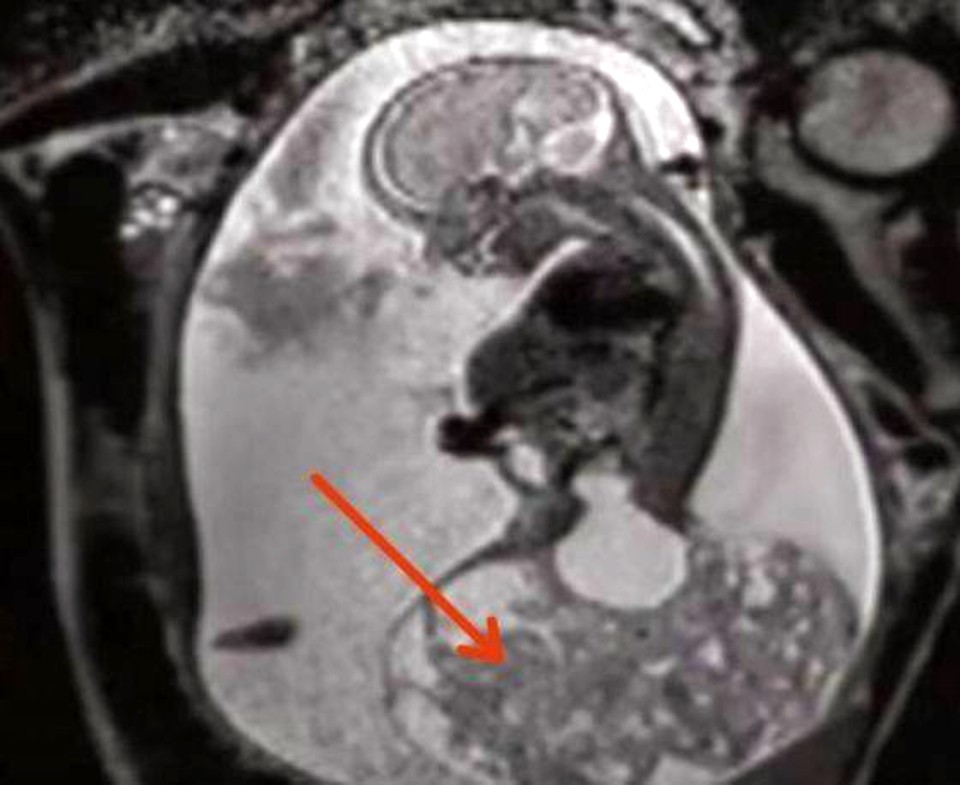

The woman’s pregnancy went smoothly until week 23, when the future mother went with emotion to a new ultrasound to find out if she will have a boy or a girl. It’s just that, as she looked at the monitor, Keri noticed a strange, ball-like formation under her fetus.

Insistent, she began to ask the doctor what that was and if there was anything wrong with her baby. Finally, the doctors gave the young mother shocking news: the child had a huge tumor, which was life-threatening because it blocked the flow of blood received from the mother.